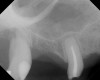

As with implant placement in general, use of a round bur is the first step in forming the osteotomy. As described above, to get verification of positioning—especially if a surgical stent is not used—a small piece of gutta percha can be placed inside this small osteotomy and a radiograph taken (Figure 1), after which the gutta percha is removed. The next step is the most critical, as it involves exposing the Schneiderian membrane. A 2-mm twist drill is used at a speed not exceeding 250 rpm, using a very light touch. Because the bone quality in the maxillary posterior is generally poor, it is usually easy to feel when the medullary bone has been breached and the dense cortical bone of the floor of the sinus has been reached. The cortical plate of the floor of the sinus should have been carefully measured with periapical radiographs presurgically, but it is usually about 1 mm in thickness. The most important and technique-sensitive part of this procedure is breaching the cortical plate of bone lining the sinus without tearing the sinus membrane. With a solid finger rest, good control, very light drilling pressure, copious irrigation, and a slow drilling speed, a slight “give” occurs once this plate of bone is breached. The full width of the twist drill should not penetrate the sinus floor; otherwise, the membrane will be torn. If it is not clear whether the membrane has been exposed, a flat-ended implant probe (Figure 2) can be used by inserting it into the osteotomy and feeling for the slight “give” or movement of the membrane. If the surgeon is not sure if the membrane is exposed, a radiographic marker can be used (Figure 3). If the membrane is significantly exposed, however, a radiographic marker should not be used, as this can inadvertently tear the membrane. The patient should also be warned not to bite down on the marker during the radiograph to avoid a membrane tear, and floss must be attached to the marker, so it can be retrieved if necessary.

Because the bone grafting materials used in this technique need physical stability during healing to support the raised membrane, there is a high probability that significant shrinkage of the graft will occur as it heals and matures if only non-demineralized material is used. For these reasons, a composite graft using calcium sulfate, DFDBA, and mineralized particulate bone is used. A 50:50 mixture by volume of mineralized bone grafting material and DFDBA is used, to which approximately 40% calcium sulfate by volume is added. A higher percentage of calcium sulfate is used relative to that described for composite grafting in other uses, because some of the calcium sulfate will wash out during bone packing. Another advantage to this composite graft is that it is not as radiopaque as a purely mineralized graft. This allows radiographic monitoring of the bone healing around the implant, which can be used to time abutment placement on the implant. This is demonstrated in Figure 4 and Figure 5, which are radiographs taken on the day of the initial surgery showing the radiographic appearance of the composite graft, implant, and graft, and in Figure 6, a 5-month postoperative radiograph with the abutment in place. The old floor of the sinus is indistinguishable from the area of new bone. Figure 7 shows a CBCT scan (Carestream Dental, www.carestreamdental.com) taken at 4 months with the old floor of the sinus indistinguishable from the new bone formed.

After about seven or eight cycles, a radiograph should be taken to verify the apical position of the sinus membrane (Figure 4). If the sinus has been raised at least 3 mm to 4 mm, the 2.8-mm twist drill should be used to remove the remaining bone at the base of the osteotomy. The osteotomy should then be widened to the final twist drill but not yet the last drill, which is the profile drill. This will allow for easier bone tapping into the sinus. The desired height of sinus membrane elevation should be such that there is about 1 mm to 2 mm of additional apical height above the implant to be placed. Usually a 10-mm implant length is sufficient. The design of the implant should have threads close to the coronal aspect of the rough surface for better initial fixation. When using a tapered implant design, the final drill is a tapered profile drill, which is the last step before placing the implant. Because it is slightly longer than the actual implant, its use could tear the membrane. To minimize the chance of tearing the membrane, a high-speed round bur and copious irrigation can be used to flatten the end of the tapered profile drill by about 1.5 mm (Figure 9) before its use. It should be used at less than 200 rpm with limited irrigation. The groove on the profile drill corresponds to the level of the bone when used. If there is minimal native ridge height, the drill should be used to a lesser depth than the groove to make sure that the site is not drilled too deeply.

A 74-year-old man presented with only about 2 mm to 3 mm of native bone below the sinus in the No. 14 position (Figure 13). The composite graft used was an approximately 50:50 mixture of DFDBA (Bio-Oss®, Geistlich Biomaterials, www.bio-oss.com) with the addition of about 40% calcium sulfate by volume (Figure 14). The implant placed (Figure 15) was a 10-mm long, rough-surfaced, platform-shifting implant (tapered 4.2 mm to 2.8 mm), and the sinus was raised about 8 mm. The postoperative radiograph taken at 4 months (Figure 16) showed some shrinkage of the graft, but no demarcation of the old sinus floor in the area.